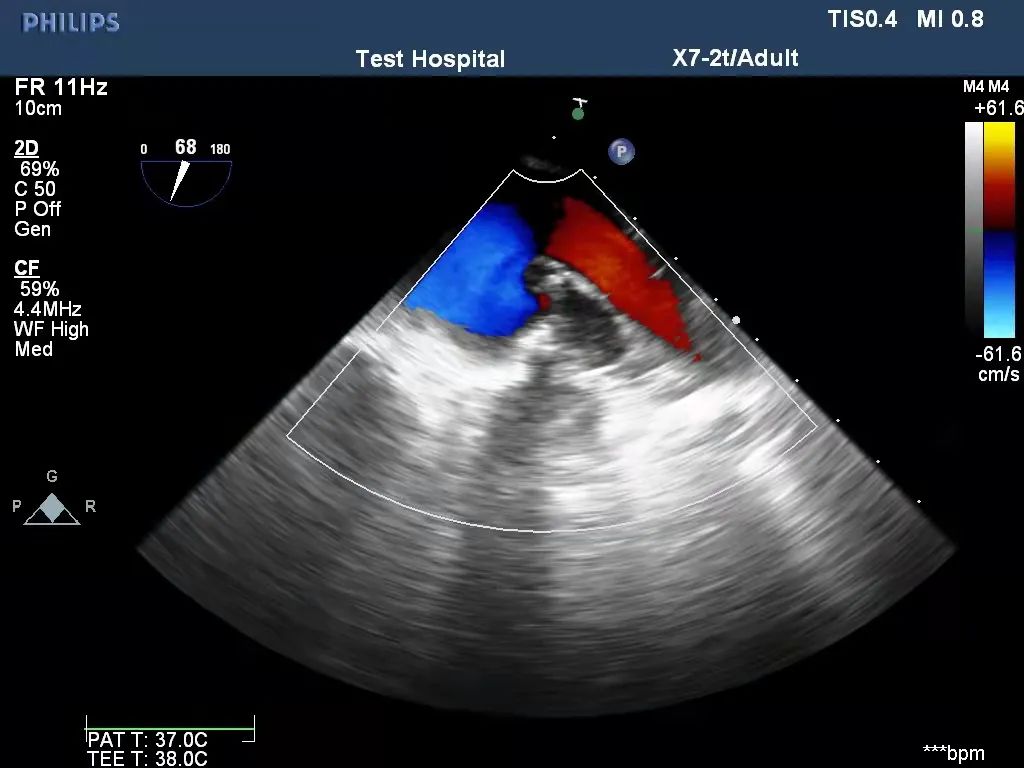

术后TEE评估左心耳闭合效果

左心耳闭合后经TEE(经食道超声)和出院前的超声评估,左心耳根部未见明显残余(残余<1cm)、闭合夹无移位,左心耳与左心房间无血流(CDFI:未见血流交通)通过,完全符合左心耳外科闭合的国际专家共识,V-Clip®首例入组圆满成功。